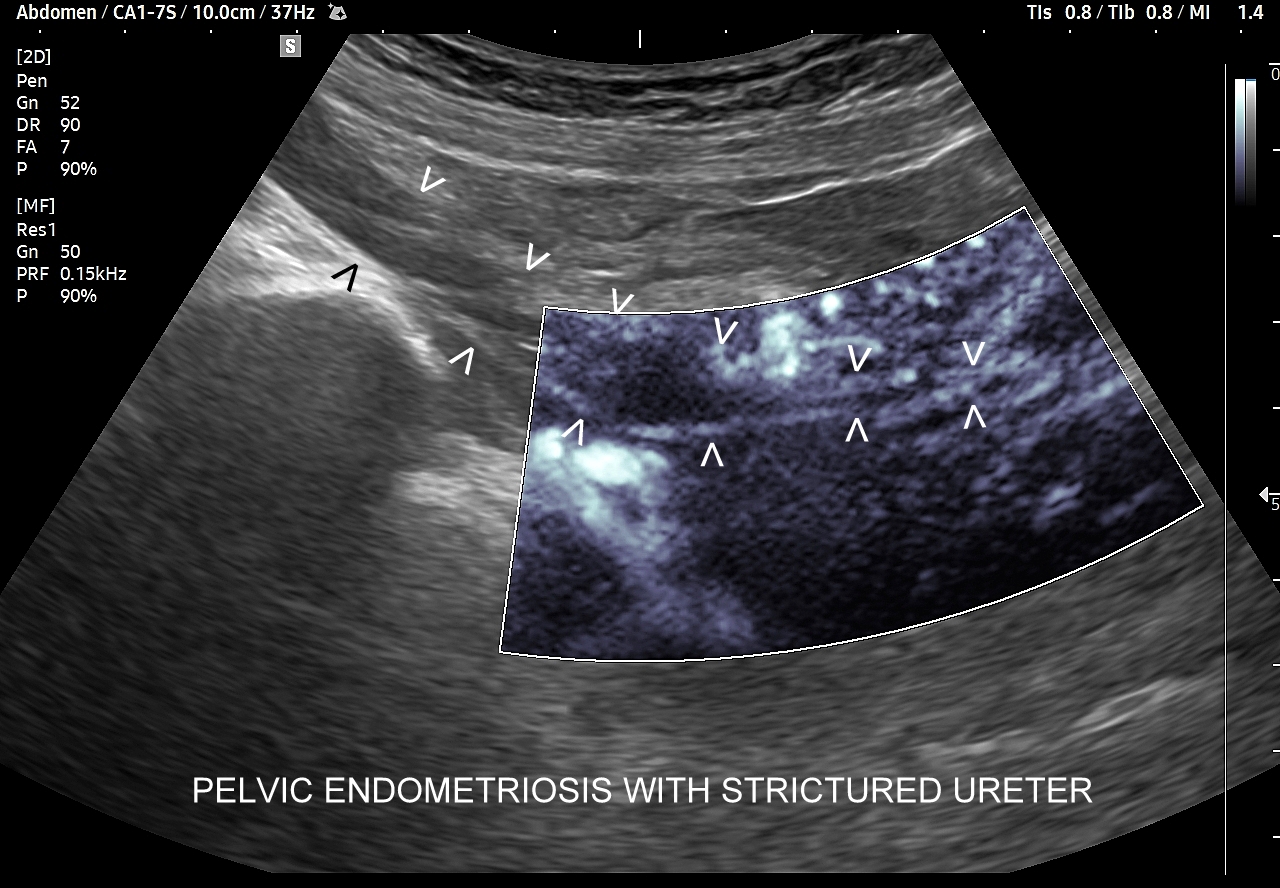

Endometrioza – metody diagnostyczne. Pierwszą linią diagnostyki endometriozy jest staranny wywiad oraz badania obrazowe w postaci USG transwaginalnego, USG przezbrzusznego oraz rezonansu magnetycznego MRI. Kombinowana czułość i specyficzność obu metod, tj. USG i MRI, sięga 90 %. Kolejnym etapem jest laparoskopia, która wykorzystywana jest zarówno jako procedura diagnostyczna, jak i lecznicza. W wyselekcjonowanych przypadkach endometriozy przydatne może być także badanie USG z kontrastem CEUS; np. do oceny zajęcia moczowodu.

W badaniu USG ogniska endometriozy zwykle przyjmują formę hypoechogennych guzków i nieregularnych mas; mogą być niejednorodne echogenicznie i zawierać drobne obszary torbielowate; w trybie color-Doppler i MVI wykazują skąpe unaczynienie.

Na skanach w niniejszym artykule zaprezentowany jest przypadek endometriozy głębokiej w miednicy mniejszej z intraluminalnym nacieczeniem dystalnego odcinka moczowodu, jego całkowitą niedrożnością i wtórnym wodonerczem. Choroba w tak zaawansowanym stadium wykryta została przypadkowo w rutynowym przezbrzusznym badaniu USG jamy brzusznej. W ramach diagnostyki różnicowej przeprowadzone zostały badanie CT, MRI oraz ureterocystoskopia z pobraniem materiału do badania histopatologicznego, na podstawie którego postawiono rozpoznanie endometriozy.